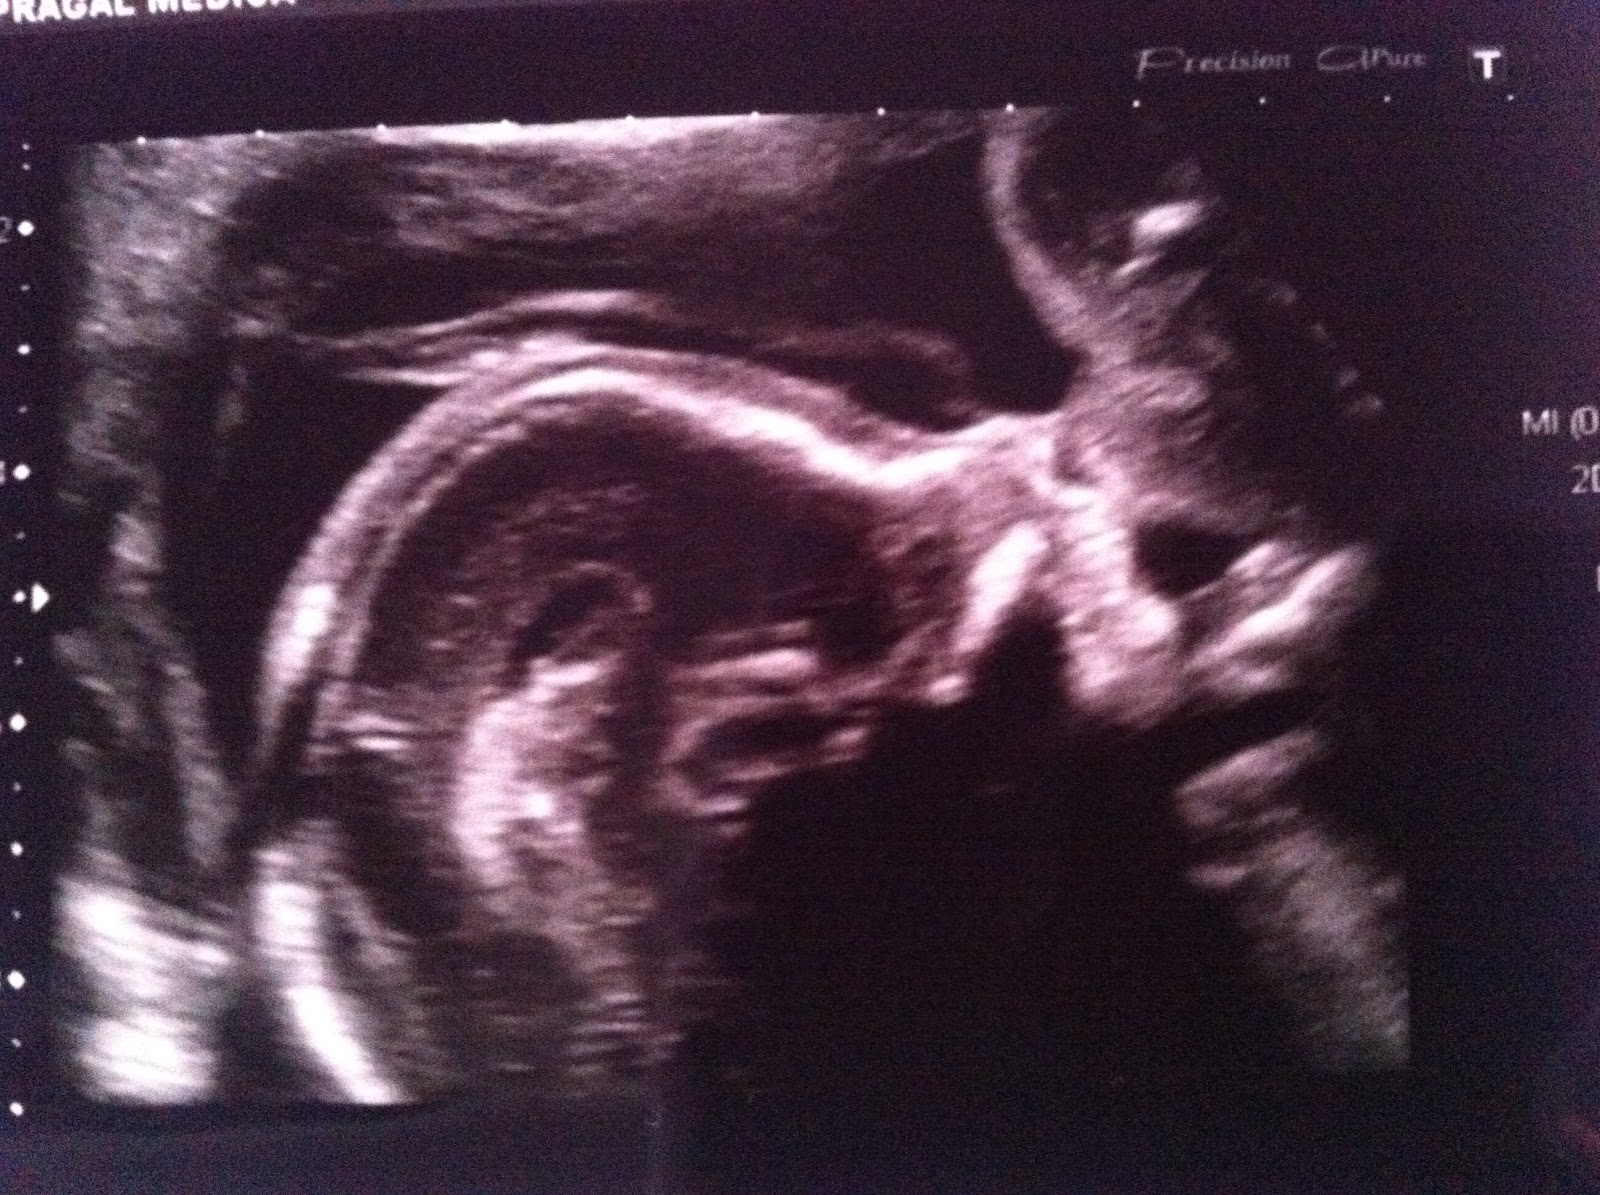

O ultrassom morfológico dosegundotrimestreé um exame de rotina feito normalmente entre 20 e 24semanasde gravidez. Serve para avaliar o desenvolvimento do bebêcombastante detalhe, incluindo os órgãos internos.

A ultrassonografia ou exame morfológicodosegundotrimestre, quandofeitoentre as 20 – 24semanas, pode ajudar a determinar o sexodobebê, verificar o risco de malformações e doenças genéticas, além das condições da placenta edolíquido amniótico.

A UltrassonografiaMorfológicadoSegundoTrimestreé um exame detalhado que avalia minuciosamente a anatomiadofeto. Realizado entre a 22ª e a 24ªsemanade gestação, este é considerado o principal exame para detecção de malformações estruturais fetais.

O estudo morfológico é um exame mais detalhado da anatomia fetal, buscando diagnosticar más-formações congênitas maiores e alterações associadas àssíndromes genéticas, como, por exemplo, a Síndrome de Down. O exame deve acontecer entre as 22ª e 24ªsemanasda gestação.